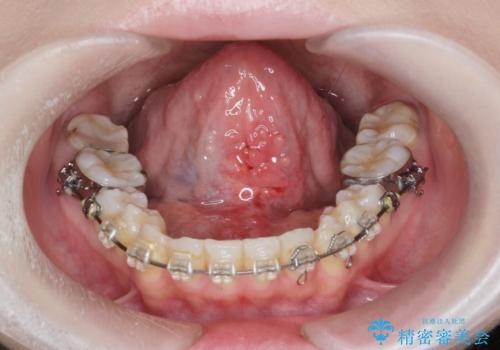

[ 舌小帯の形成術 ] 短い舌の改善をしたい

担当医 大元洋佑

![[ 舌小帯の形成術 ] 短い舌の改善をしたいの症例 治療後](https://seimitsushinbi.jp/wp/wp-content/uploads/2024/01/52db9b03a5d3a93572f61dbac2597f07-500x350.jpg?v=1706348765)